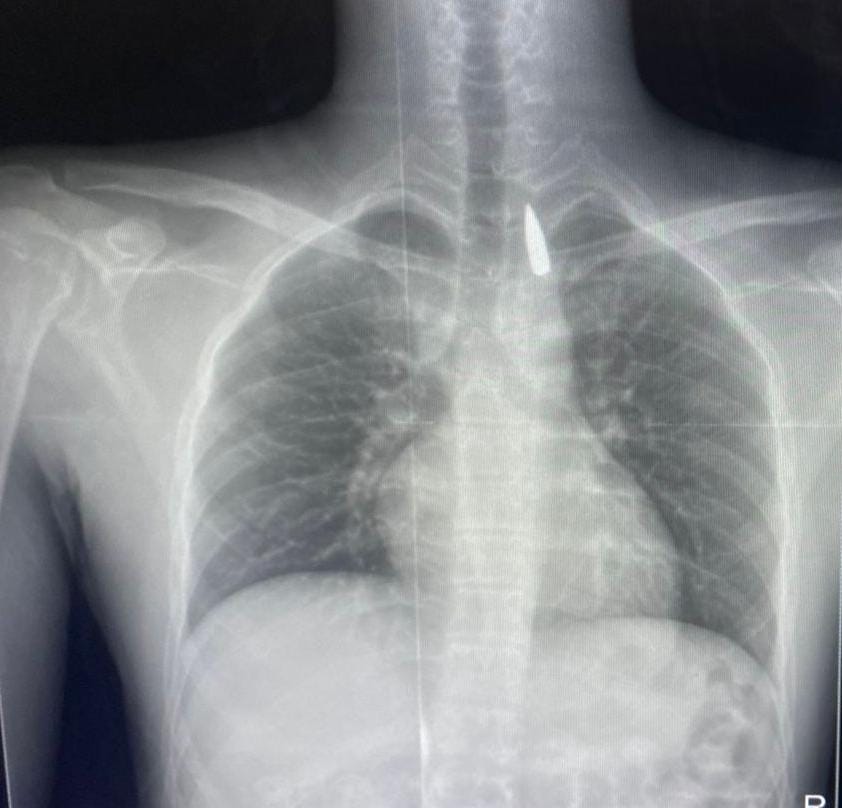

وأوضح الدكتور تامر عبد الله، عميد كلية الطب ورئيس مجلس إدارة المستشفيات الجامعية، أنه في يوم 21 أكتوبر 2025 تمكن فريق من أطباء قسم جراحة القلب والصدر والتخدير والمعاونين من إجراء جراحة دقيقة بالغة الخطورة لأحد المرضى المحجوزين من قطاع غزة، والذي كان قد تعرض لإصابة بطلق ناري في الرأس منذ فترة، استقر المقذوف على إثرها داخل تجويف القفص الصدري قرب الشريان الأورطي، وهو أكبر وأهم شرايين الجسم والمسؤول عن تغذية جميع الأعضاء الحيوية، وأضاف أن الفريق الطبي، رغم دقة الحالة وتعقيدها، نجح في استخراج المقذوف بأمان بعد عملية جراحية نادرة استمرت عدة ساعات داخل المستشفى الجامعي الجديد، حيث خضع المريض بعدها للرعاية الطبية اللازمة، وحالته حاليًا مستقرة وتحت المتابعة الدقيقة من الفريق المختص.